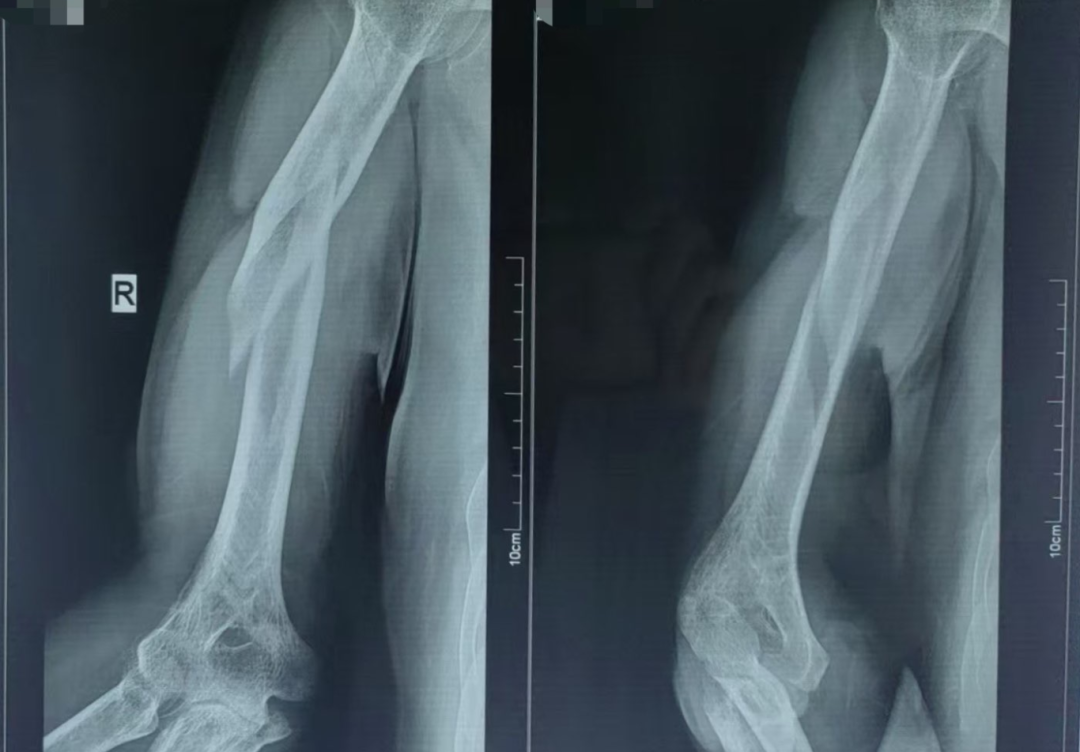

阳光讯(记者 郑亚雷 通讯员 曾雪琴)近日,57岁的夏先生因意外摔伤,右臂剧痛难忍、活动受限,在家人的陪同下紧急前往西安市红会医院南院区就诊。经影像学检查,被确诊为右肱骨骨折,骨折端移位明显、成角畸形,病情复杂。

在董博主任医师和周健副主任医师的精准操作下,通过专业的手法复位技术,成功将移位的骨折端恢复至正常解剖位置,随后为患者佩戴外固定支架进行稳定固定。复位后的X线片显示,骨折对位对线良好,患肢末梢血运正常,治疗效果显著。